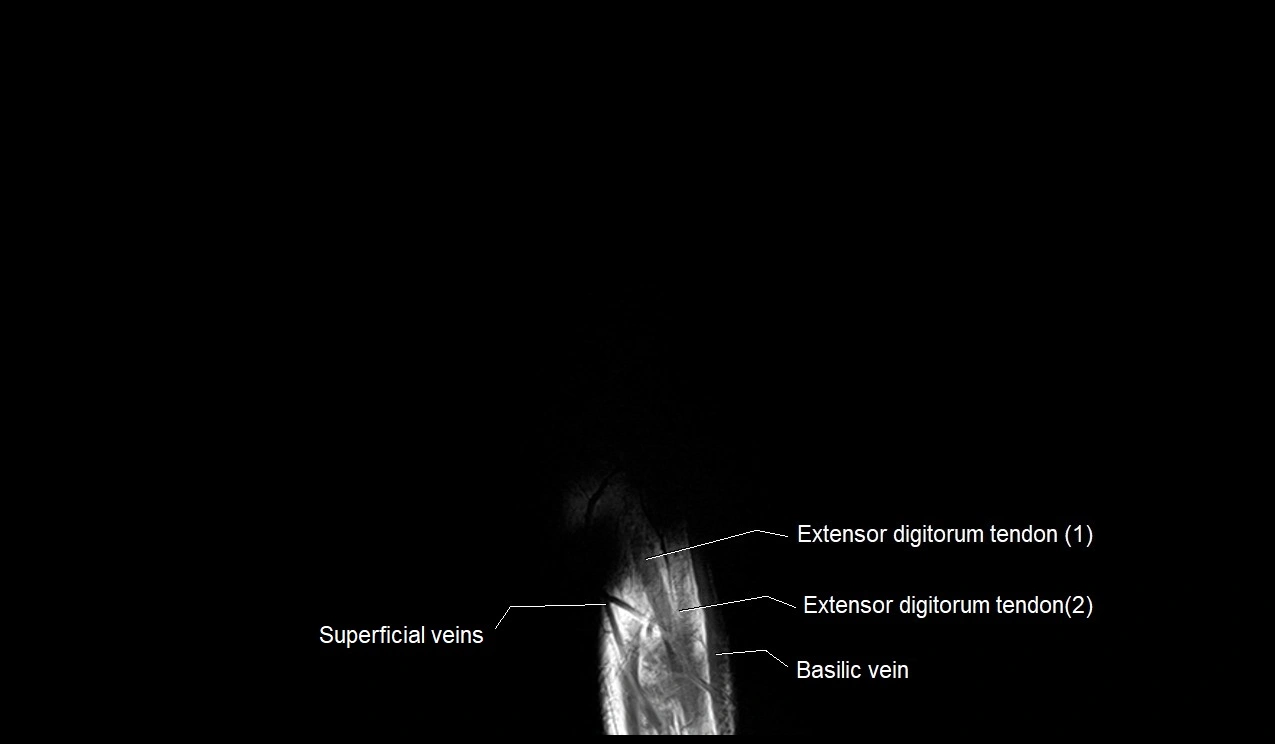

MRI image